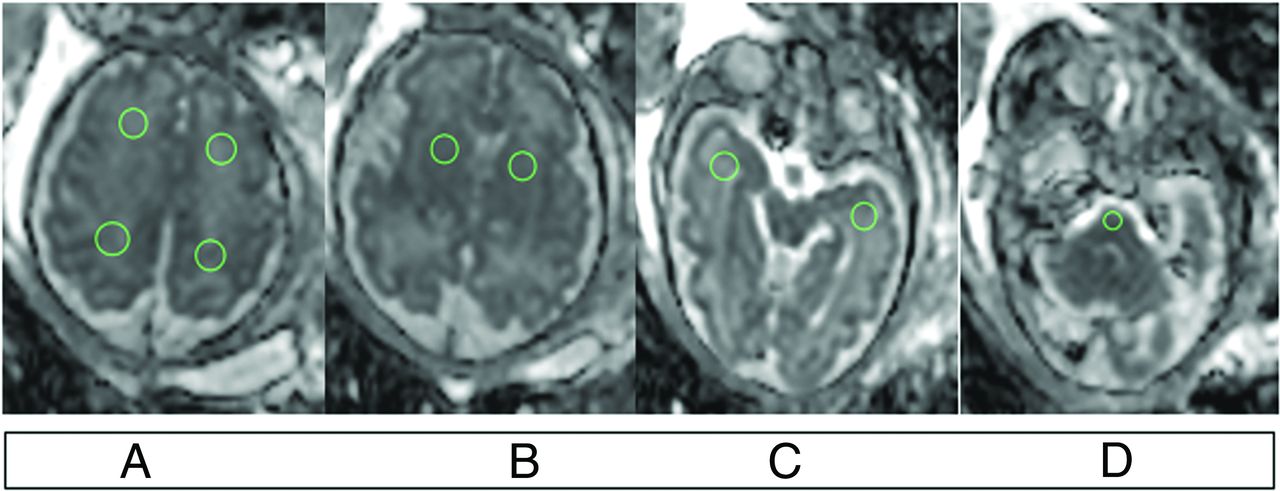

The acquired DWIs were transferred in DICOM format to the IntelliSpace portal, Version 10 (Philips Healthcare), and ADC maps were generated using the MR diffusion tool. To avoid intervendor variability in diffusivity metrics, we analyzed diffusivity data only from studies acquired on the Philips scanner (94 of 106 fbMRIs in our study). Nine circular ROIs were manually placed on the following areas of the fetal brain (Fig 2): bilateral frontal WM, parietal WM, temporal WM, basal ganglia, and pons. ROIs ranged from 10 to 57 mm2 (mean, 37.1 [SD, 12.7] mm2). ADC values were measured in the same regions of the bilateral cerebral hemisphere and basal ganglia; then, mean ADC values were calculated for each ROI. To validate the consistency of measurements and the reliability of results, 2 observers independently evaluated the first 13 consecutive fetuses (neuroradiology fellow, B.D., and a senior radiology resident, M.S.). Interobserver variability was assessed by the interclass correlation coefficient (ICC). We considered an ICC value of ≥0.8 as excellent agreement. ADC measurements were not available in fetuses with either degraded DWIs (ie, marked motion artifacts or field inhomogeneity) or fbMRI performed on different magnets.

ROI placement on ADC map of DWI. A, Frontal and parietal lobes. B, Basal ganglia. C, Temporal lobes. D, Pons.